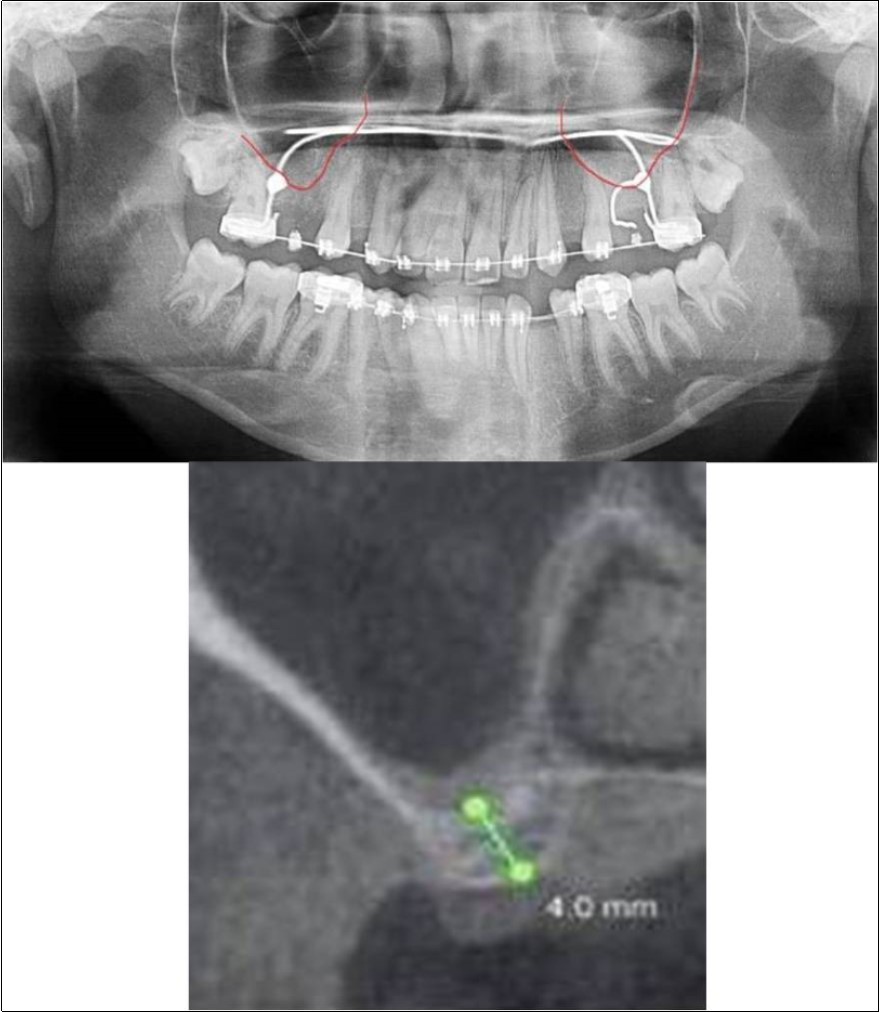

A 19 years old young female patient reported to the Department of Oral and Maxillofacial Surgery, D.A.P.M.R.V Dental College and Hospital seeking options for replacement of her missing right and left upper first molars with a fixed prosthesis as she was uncomfortable with the removable partial denture i.r.t 16 and 26. The teeth were extracted 6 months ago because of gross loss of crown structure and poor prognosis for root canal treatment. Patient was also undergoing fixed orthodontic treatment for proclined upper anteriors. Patient did not give history of any existing sinus pathologies. All possible rehabilitative options were explained to the patient and a treatment plan of replacement of missing teeth with implant supported prosthesis using two dental implants was finalized.

Clinical and Radiological Assessment:

1.Partially edentulous maxillary arch with missing 16 and 26;

2.Increased pneumatisation of right and left maxillary sinus;

3.Height of available bone-

16 region: 6.5mm;

26 region: 6.2mm;

4.Transverse thickness of available bone (CBCT evaluation)-

16 region: 8.3mm;

26 region: 10.5mm;

5.Fixed orthodontic appliance;

6.Inter-ridge space adequate to place implant (11mm).

Treatment:

Patient underwent the procedure of indirect sinus elevation using sinus osteotomes in relation to 26 region. Calcium phosphosilicate putty was dispensed as the graft material through the crestal osteotomy site to maintain the elevated sinus membrane followed by placement of 5 x 10mm dental implant under local anaesthesia and strict aseptic protocols. The implant was allowed to osseo-integrate for a period of six months during which the patient was followed-up periodically and was assessed for peri-implantitis, crestal bone loss and mobility. Patient was taken-up for direct sinus elevation via lateral window approach for sinus augmentation i.r.t 16 region. Under aseptic conditions and local anaesthesia, lateral wall of maxilla was exposed after muco-periosteal flap elevation. A window was created of 1cm diameter corresponding to apical aspect of 16. Sinus membrane was identified and elevated using sinus elevators and reamers without perforating the lining. Once the sinus membrane was elevated, phosphosilicate putty was dispensed through the lateral osteotomy site as the graft material to achieve an augmentation of 1cm assessed clinically and confirmed using post-operative OPG. At the end of 6 months, a repeat CBCT scan was advised to evaluate the increase in bone height. (Figure 13a,b, pre-treatment; Figure 14a,b, post-treatment)

Figure 13.(a,b) Pre-treatment OPG and cross section of CBCT showing residual alveolar bone height for Case No.4;

Figure 14.(a,b) Post-treatment OPG and cross section of CBCT showing residual alveolar bone height for Case No.4;